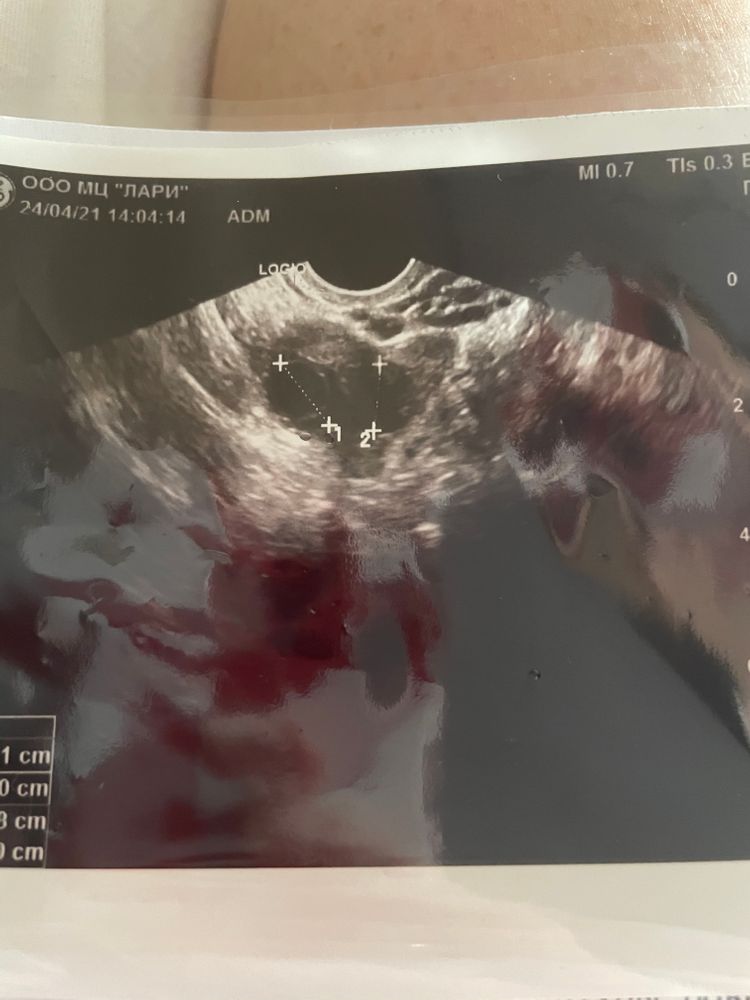

сходила на фолликулометрию 9 дц, в левом яичнике два доминанта, 13 мм и 11 мм , но врач сказала Надежда на тот который 13 мм, не из за размера, а по форме , ободок и тд, сказала он с яйцеклеткой. Мне по фото кажется и второй такой же .. кто разбирается в этой теме подскажите отличие фолликулов на узи ?

Интересный доктор. Яйцеклетку можно увидеть только в лабораторных условиях, и не каждый фолликул может её иметь. А эта увидела на аппарате у фрлоикула 13 мм.

Ангелина, по косвенными признакам она сказала, конечно саму яйцеклетку не видно. По оболочке и тд